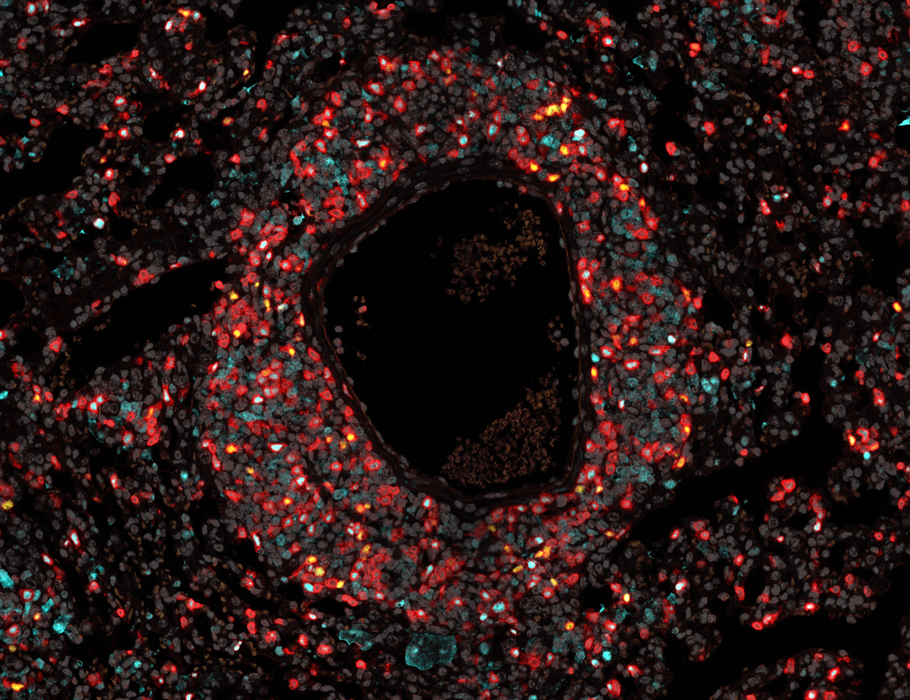

Crosstalk between #Tregs and #ILC2s is necessary to curb #inflammation in allergic disease, mouse research suggests.

Learn more in Science #Immunology: scim.ag/7Ku